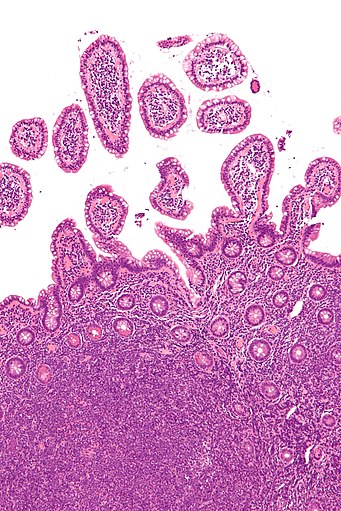

Nehodgkinské (non-hodgkinské, non-Hodgkinovy) lymfomy (NHL) jsou velkou podskupinou lymfomů. Druhou podskupinu tvoří Hodgkinův lymfom. Dle biologického chování lze nehodgkinské lymfomy rozdělit do dvou skupin: Lymfomy nízce maligní (nízce…

Non-Hodgkinovy lymfomy (zkráceně NHL) je skupina onemocnění způsobujících rakovinu krve, která zahrnuje všechny lymfomy kromě Hodgkinových. Různé NHL se velmi liší v nebezpečnosti, od nebolestivých po velmi agresivní. Non-Hodgkinovy lymfomy byly popsány v roce 1982 dokumentem Working Formulation, který uváděl 16 různých typů NHL. Od té doby však tato klasifikace zastarala a v dnešní době se používá jen pro statistické účely pro srovnávání s předchozím výskytem nemocí. Klasifikace, kterou roku… Wikipedie